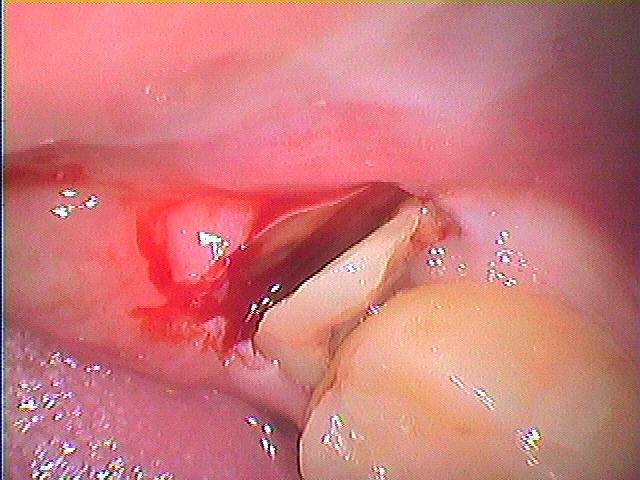

左下の奥の親不知 虫歯になっているので抜いたほうがいいといわれながらも、、、、そこの歯医者では抜けないとのこと|お知らせ |広島市安佐南区の歯科医院 左下の奥の親不知 虫歯になっているので抜いたほうがいいといわれながらも、、、、そこの歯医者では抜けないとのこと トップ お知らせ・ブログ お知らせ 左下の奥の親不知 虫歯になっているので抜いたほうがいいといわれながらも、、、、そこの歯医者では抜けないとのこと 左下の奥の親不知 虫歯になっているので抜いたほうがいいといわれながらも、、、、そこの歯医者では抜けないとのこと 問題の歯になります パノラマになります 虫歯が存在 歯冠部を分割抜歯していきました 歯冠部を分割して取り出し、根部をを除去していきました 縫合して終了となります 取り出した歯になります 皮質骨が付いてきました Web診療予約 初めての方へ 選ばれ続ける理由 院内設備について 歯が痛いしみる一般歯科 歯がぐらぐらする歯周病 健康な歯を保ちたい予防歯科 子供の虫歯予防をしたい小児歯科 銀歯をセラミックに審美歯科 白い歯を目指しませんか?ホワイトニング 矯正専門医がいるので安心矯正歯科 抜けた歯を補いたいインプラント・入れ歯 医院案内 スタッフ紹介 メリィハウス歯科クリニックオフィシャルホームページ ラベンダー歯科クリニックオフィシャルホームページ お知らせ・ブログ ホーム 診療科目 一般歯科 歯周病治療 予防治療 小児歯科 審美治療 ホワイトニング 矯正歯科 入れ歯・インプラント マウスピース矯正 初めての方へ 院長・スタッフ 設備紹介 医院案内・アクセス メニューを閉じる